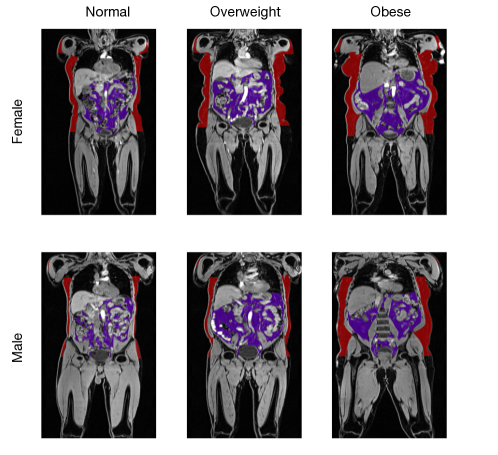

For each subgroup of the dataset, one reference image has to be selected. This reference image can significantly impact the registration performance and must be carefully selected to optimally represent the distribution in the cohort. We use the phenotypic data of the subjects to identify the most representative reference for each group. All reference subjects represent the median age, weight, height, BMI, and body fat percentage in the respective subgroup of the dataset (e.g. overweight females). The specific properties of all selected reference subjects are summarised in Table 2. A medical expert then assessed the selected references, evaluating whether the muscle and fat proportions were representative of the respective subgroup. Figure 2 shows the final reference images selected for the atlas generations, overlayed with the corresponding abdominal fat segmentations. We can see apparent differences in anatomy and fat distribution between the groups, highlighting the necessity to separate the dataset.

Refer to caption

Figure 2: Reference images of the different subgroups of the dataset; The first row shows the female subjects and the second row the male subjects of the respective BMI groups (columns) overlayed with their respective labels of fatty tissue. Red: abdominal subcutaneous fat, purple: abdominal visceral fat.